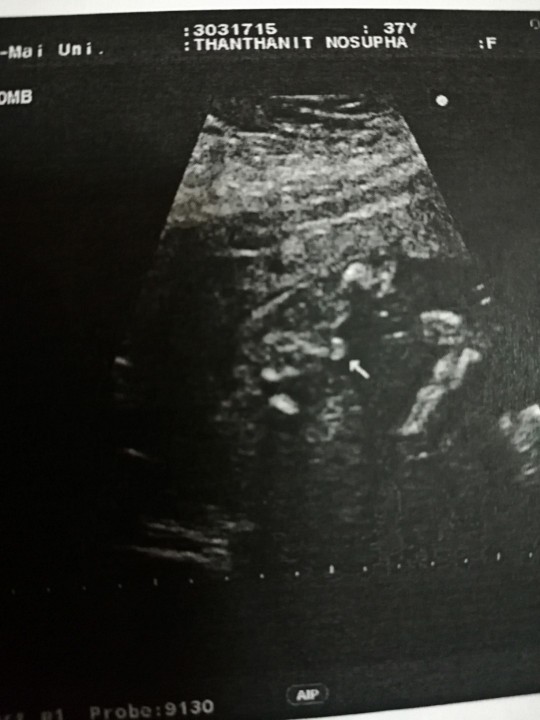

ผู้ชายจ้า 32week

เห็นจู๋ชัดเลยจ้า